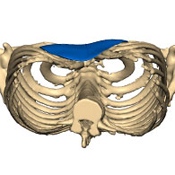

Vista 3D de un Pectus Excavatum con implante